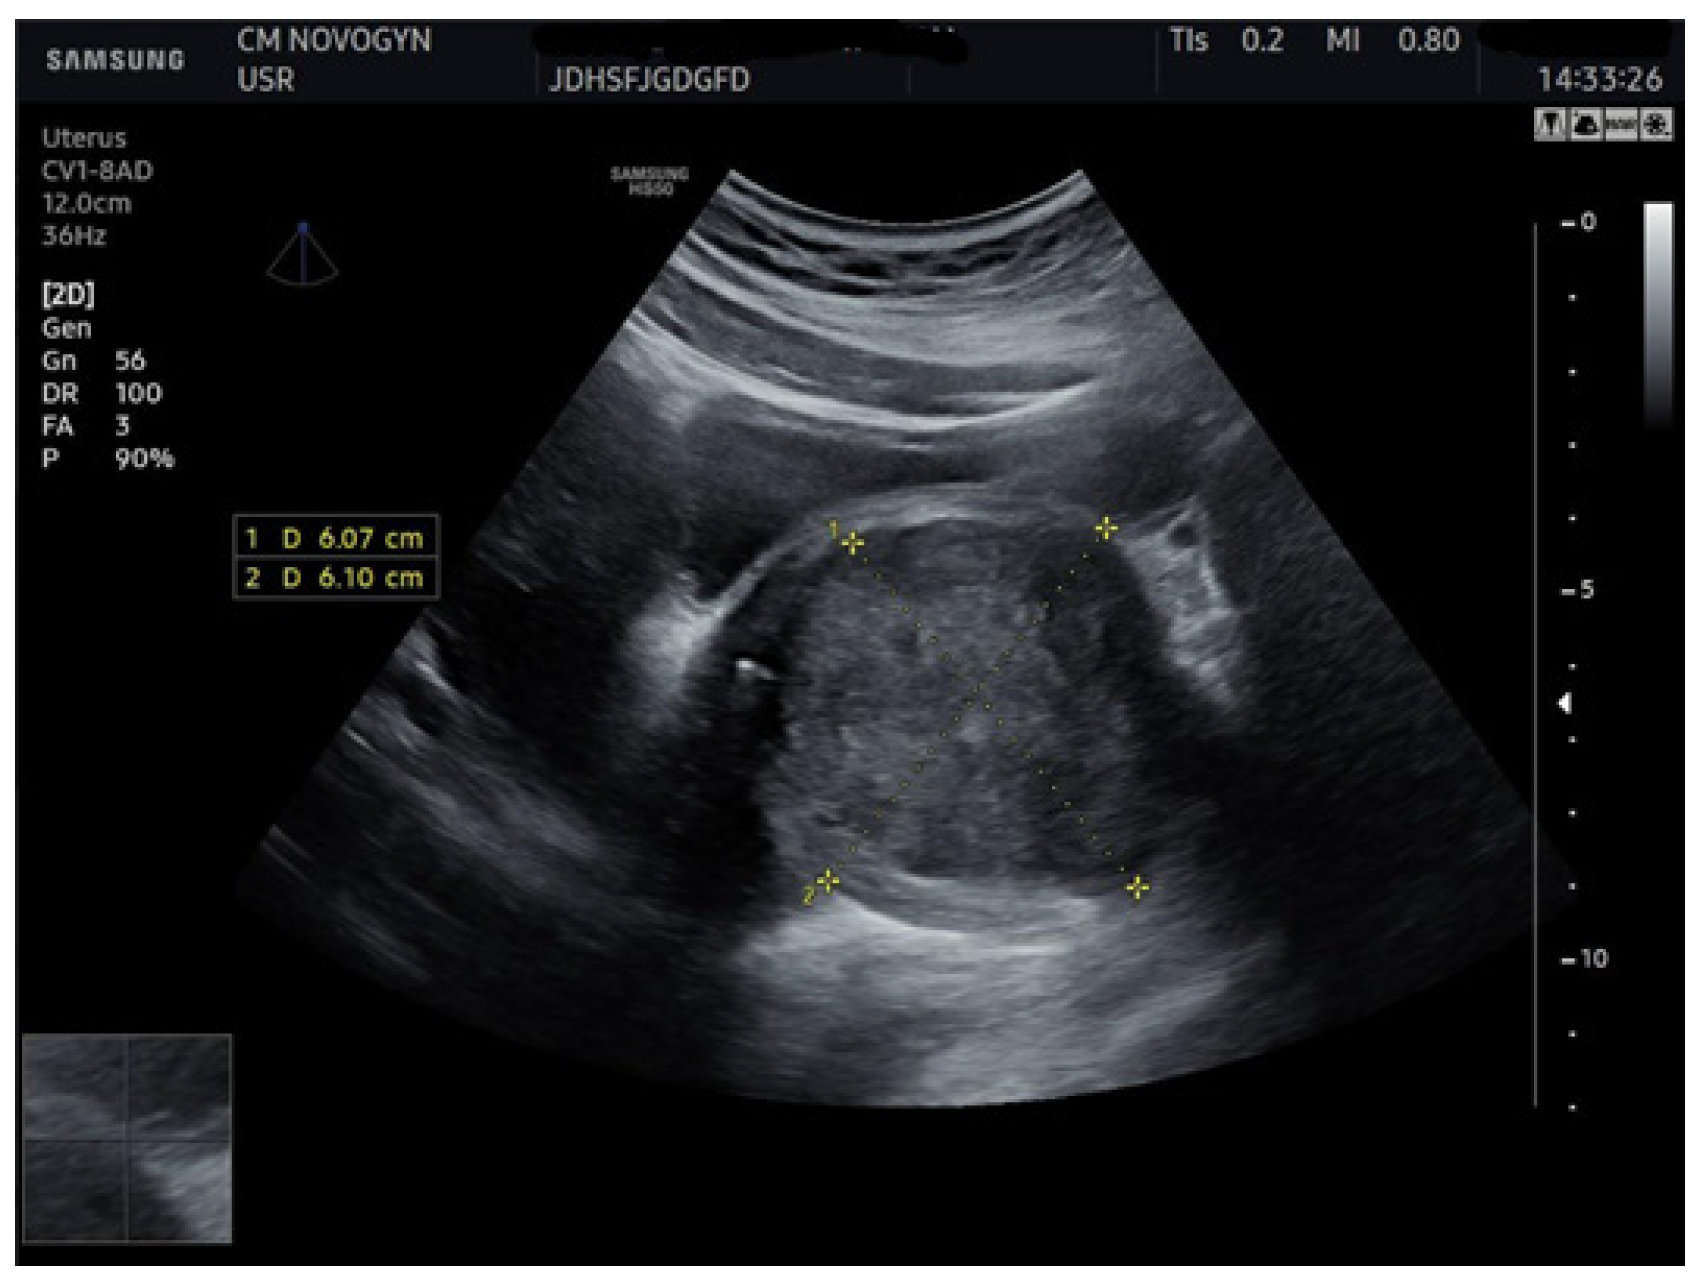

2.4. Imaging Studies

3.1. Imaging Characteristics and Diagnostic Precision